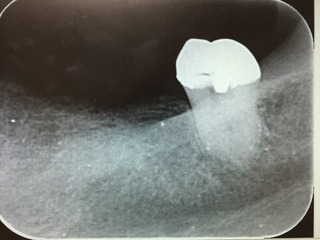

歯の欠損はインプラント治療で回復

歯を失えばその後に控えている治療としては義歯、ブリッジ、インプラント治療もしくはなにもやらないという4つの選択肢があります。

今回はインプラント治療を選択しました。長年義歯の生活から解放されたいということでした。今の入れ歯を使いながらインプラント治療はできます。

義歯の歯のない部分にインプラント手術で入れ込んだあとに義歯の床のピンク色の部分を削って義歯が使えるようにします。3カ月経過後にインプラント部分の歯型をとって完成した時に義歯の使用を中止するので歯が全くなくなってしまう期間はゼロです。